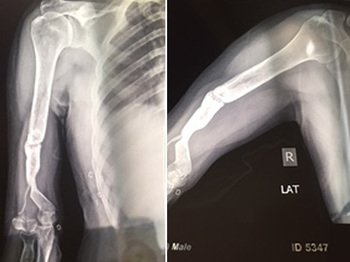

Fractures that have had a delay of more than 3 weeks to seek medical attention from the time of the accident or injury cases which have been mismanaged at the initial stage. Special care is required for neglected fractures.

These surgeries are the most difficult and challenging to treat. Dr Narula uses 3 generation techniques with special implants and Grafts to treat such complicated cases.